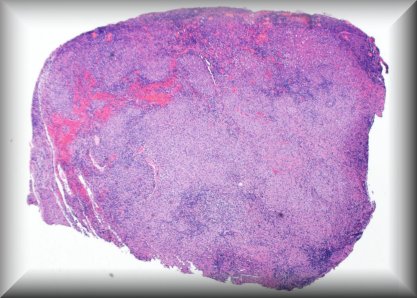

Maria del Valle Estopinal (Irvine, California): Malignant epithelioid tumor involving the left lower eyelid. |